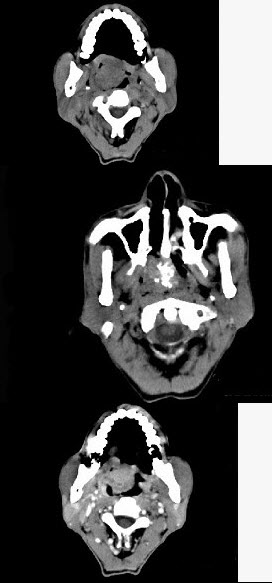

男性,57岁,睡觉打鼾,近来加重,CT扫描如图所示,请选择正确的描述和答案()。

A:鼻咽腔偏右侧可见类圆形软组织块影

B:肿块内密度尚均匀,其上方见较多钙化影

C:肿块边缘大部清楚,邻近结构未见明显受侵

D:考虑为鼻咽癌

E:考虑为鼻咽部多形性腺瘤